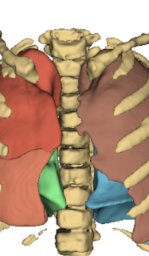

![]() |

| Real CT | L1 | Perceptual | AFP TotalSeg | AFP NaviAirway | AFP Navi + HAL |

Table 3 and Fig. 5 present a comparison of the models on the reconstruction of lung anatomical regions using the TotalSegmentator (TotalSeg) pipeline with Dice score and NSD. The model trained with the AFP loss using TotalSeg’s embeddings provide the best performances. For example, when reconstructing bones, this model achieves a NSD of 0.629, outperforming the L1 loss model (NSD: 0.493) as well as perceptual loss (NSD: 0.499). A combination of AFP loss using NaviAirway and HAL’s embeddings also delivers positive results, whereas other models exhibit notably poorer reconstructions especially in the bones.